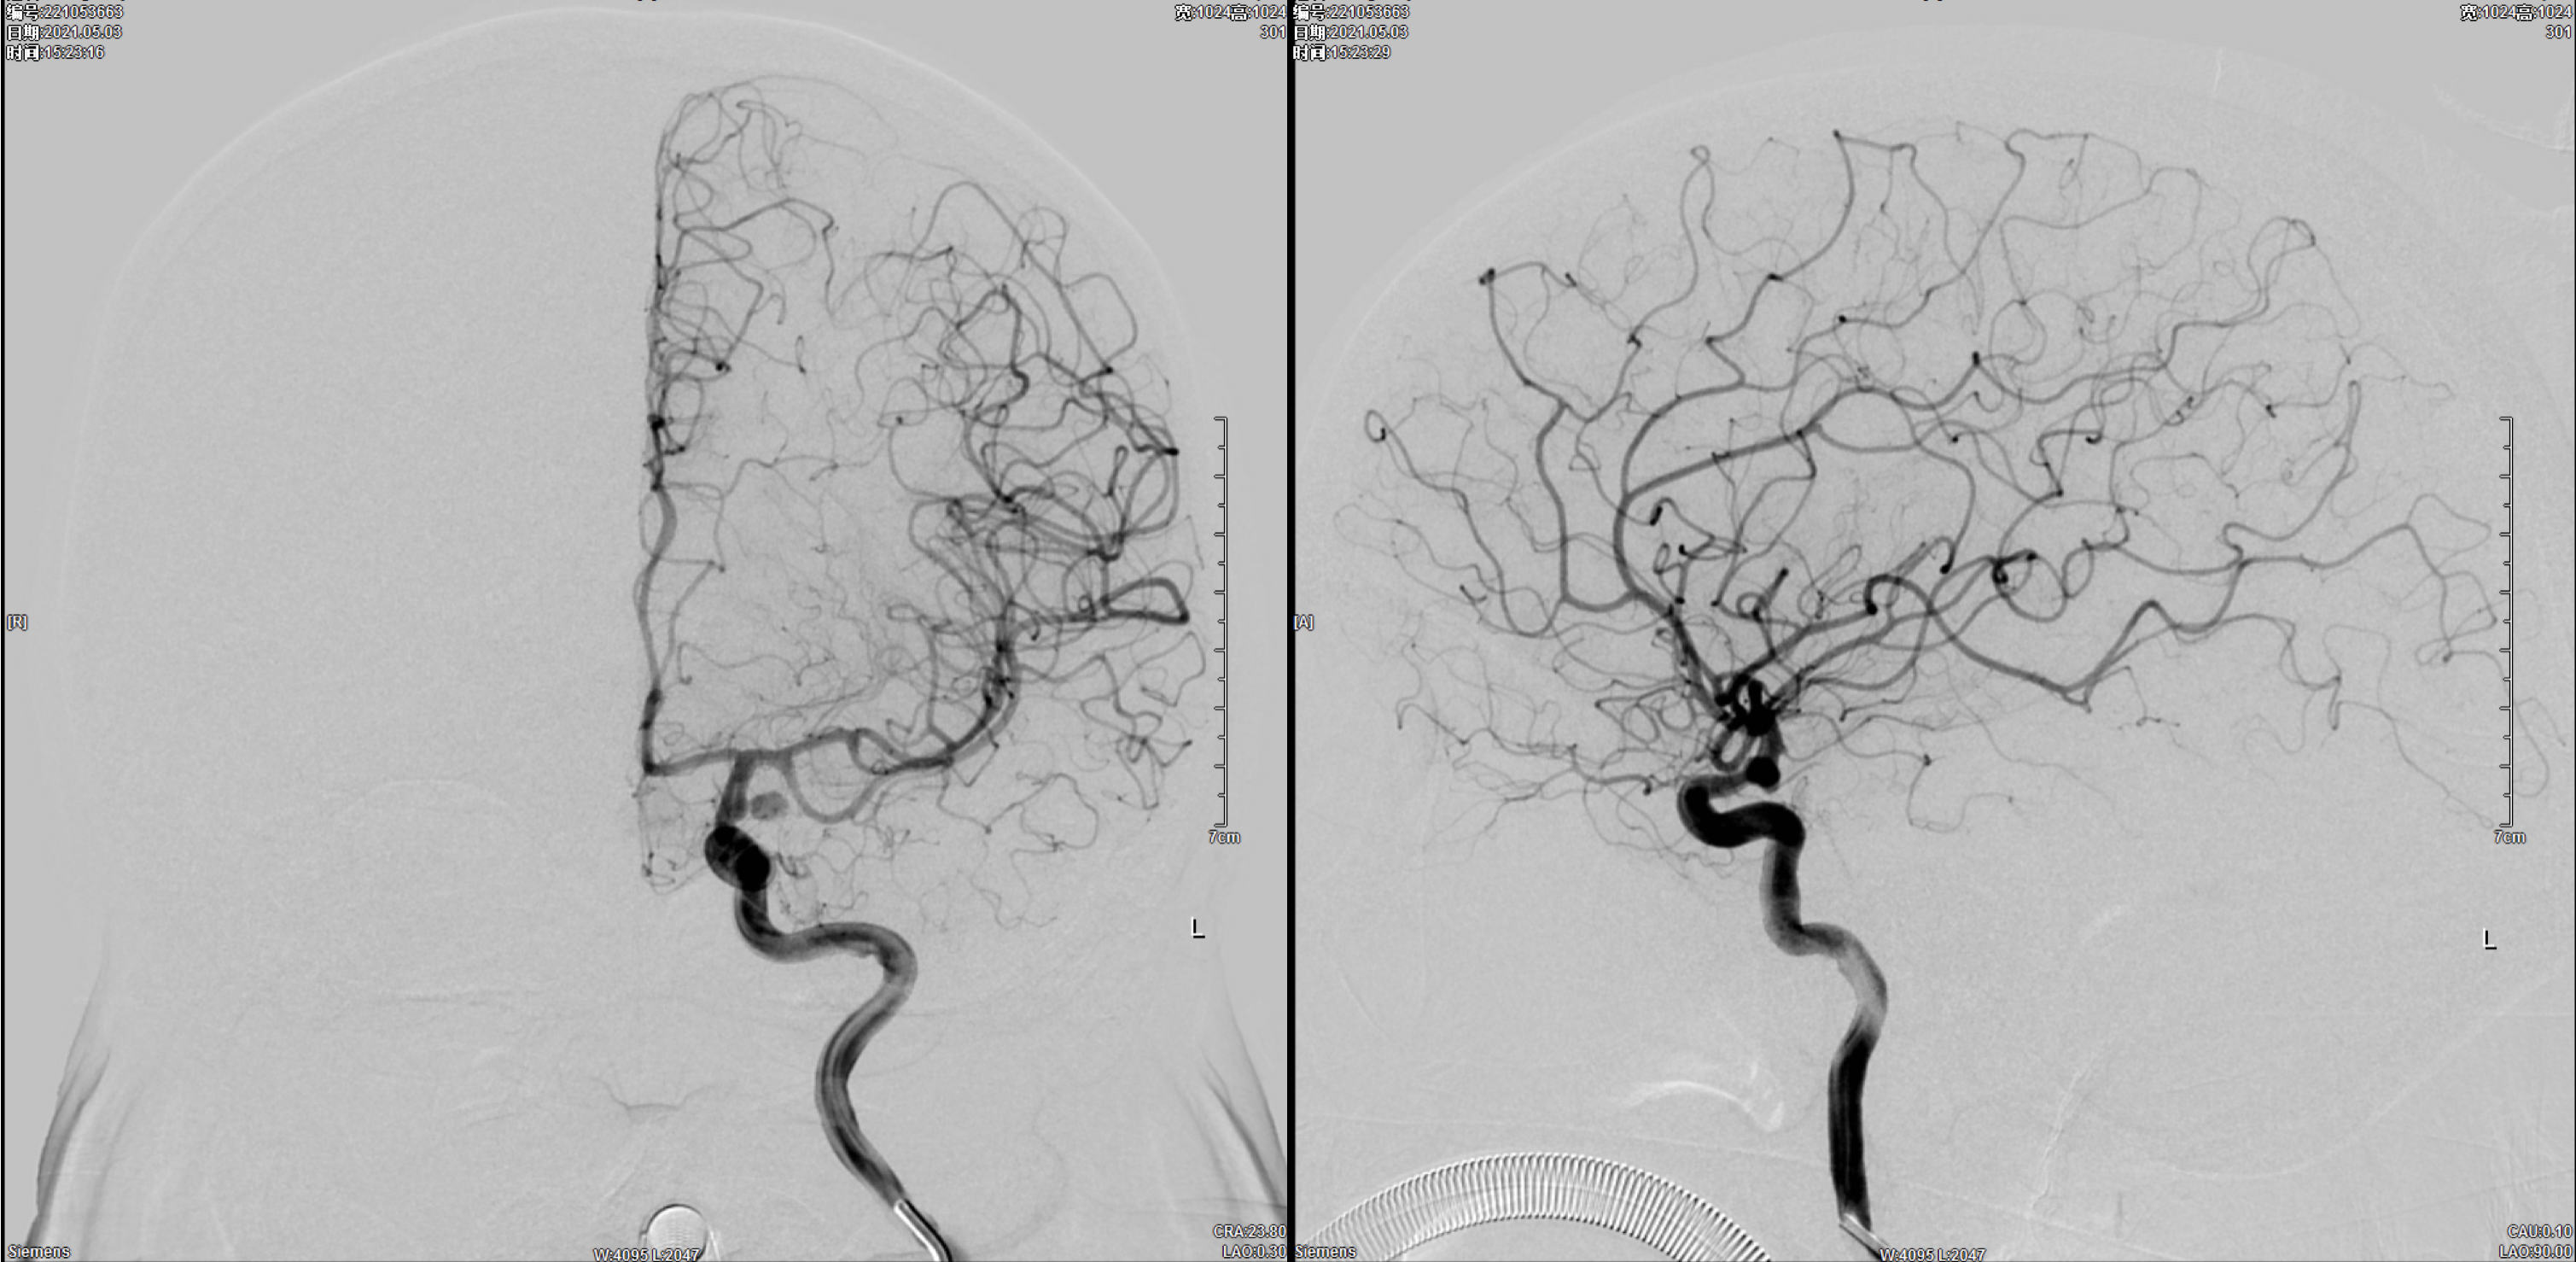

右侧颈内动脉正侧位造影:颈内动脉多发动脉瘤(眼动脉段及后交通段)。

左侧颈内动脉正侧位造影:颈内动脉后交通动脉瘤。